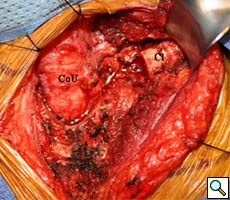

Intraoperatively, the gastric conduit was noted to be intimately compressed by the left SCJ (Figure 3A). The insertion of the sternocleidomastoid and other strap muscles were divided using electrocautery and the conduit was carefully bluntly dissected off the posterior sternum and left SCJ. The manubrial and clavicular segments of the SCJ were then resected, revealing the conduit underneath in good condition (Figure 3B). Care was taken to preserve the left internal mammary artery. Intraoperative EGD confirmed easy passage of the scope through the cervical anastomosis and into the gastric conduit with reduced extrinsic compression. Saline irrigation into the field and air insufflation of the conduit was used to confirm conduit integrity. A Savary-Gilliard guidewire was endoscopically passed and the anastomosis was carefully dilated using 42, 48, and 54 French (Fr) Savary-Gilliard bougie dilators (Cook Medical, Bloomington, IN) with minimal resistance. After removal of the guidewire, a 52 Fr Maloney dilator (Medovations, Milwaukee, WI) was also passed through the conduit without difficulty.